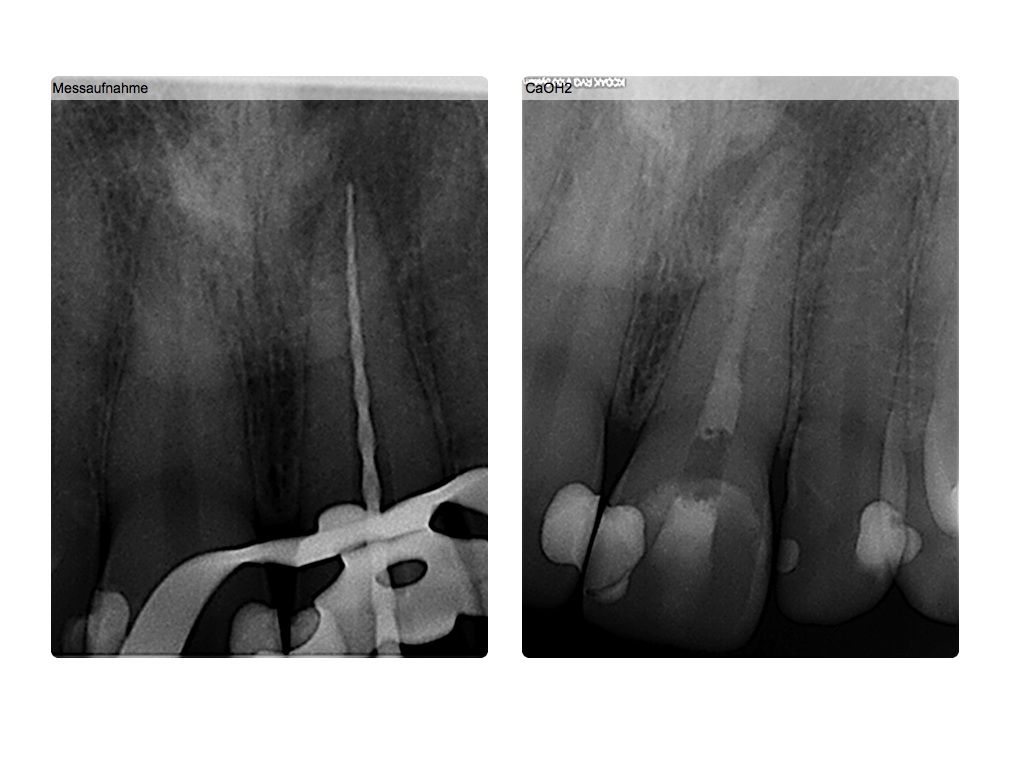

3 Veröffentlicht 13. Januar 2014 am 1024 × 768 in Hätten Sie es gesehen? (2) Messaufnahme 1 und Ca(OH)2